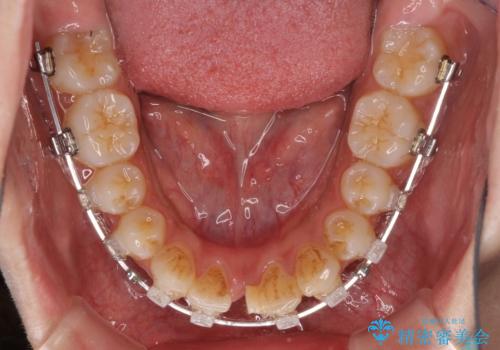

- クリアブラケット

- 2年2ヶ月

口元の突出感がありと、下顎の前歯が1本欠損していました。

上顎の前から両側の前から4番目の歯と、下あごの前歯を1本抜歯して、口元をすっきりさせる計画としました。